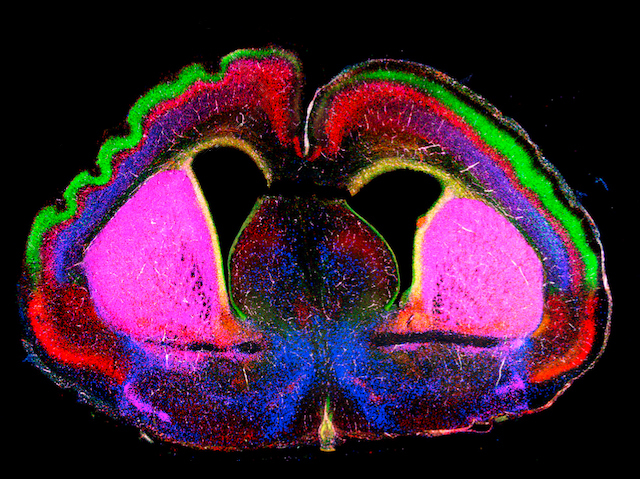

Scientists have identified a receptor that plays a crucial role in how our brains fold during early development. This folding enlarges the brain’s surface area, creating room for the neurons that carry our thoughts and memories. To explore how folds develop, researchers studied the brains of mice. Unlike people, mice have smooth brains. The team found that they also have higher levels of a receptor, called FLRT. This was shown to help neurons to stick together and move in an orderly way from the inner brain (red), to the outer layer (green) during development. When mice were engineered to have lower than normal levels of FLRT receptors, to match those found in people, the mouse neurons formed weaker bonds. This allowed them to move freely towards the outer layer, where their build up created pressure. The study suggests it’s this pressure that causes brain tissue to buckle and fold (top left).